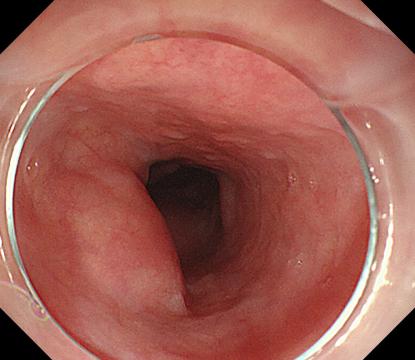

直腸側向發育性腫瘤 內鏡下黏膜下剝離術后創面

內鏡下黏膜剝離術(ESD):治療巨大平坦息肉,早期癌及癌前病變,黏膜下腫瘤等。